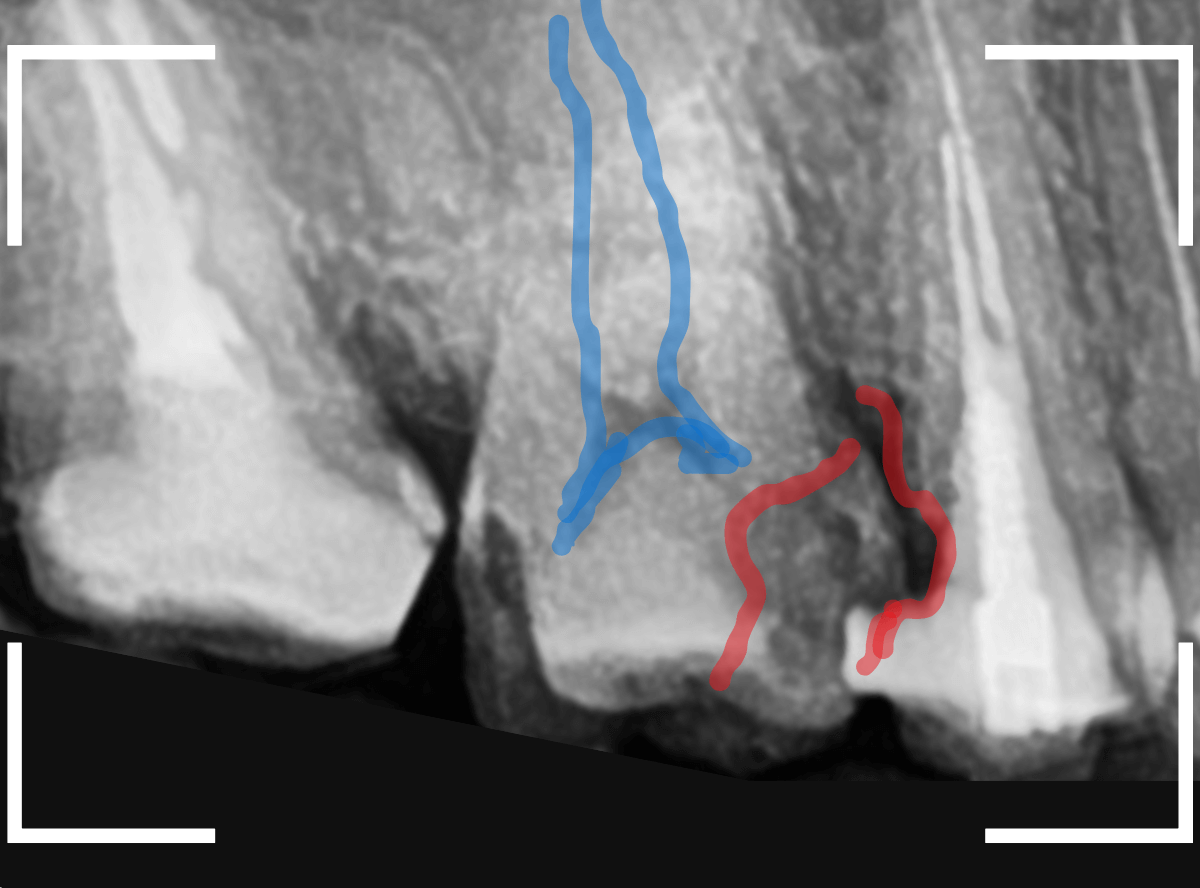

レントゲン写真で確認します。

青い線が歯の神経、赤い線が虫歯です。

おやしらずがあった際にはわかりづらかったですが、歯の後ろ側のおやしらずが重なっていたところが虫歯になっているのがわかります。

おやしらずが原因で、このように手前の歯が虫歯になってしまう事が多いために、抜歯を勧められる事が多いのです。

そして、虫歯の部分におやしらずが被さっていたために、しみる症状などを感じなかったのです。